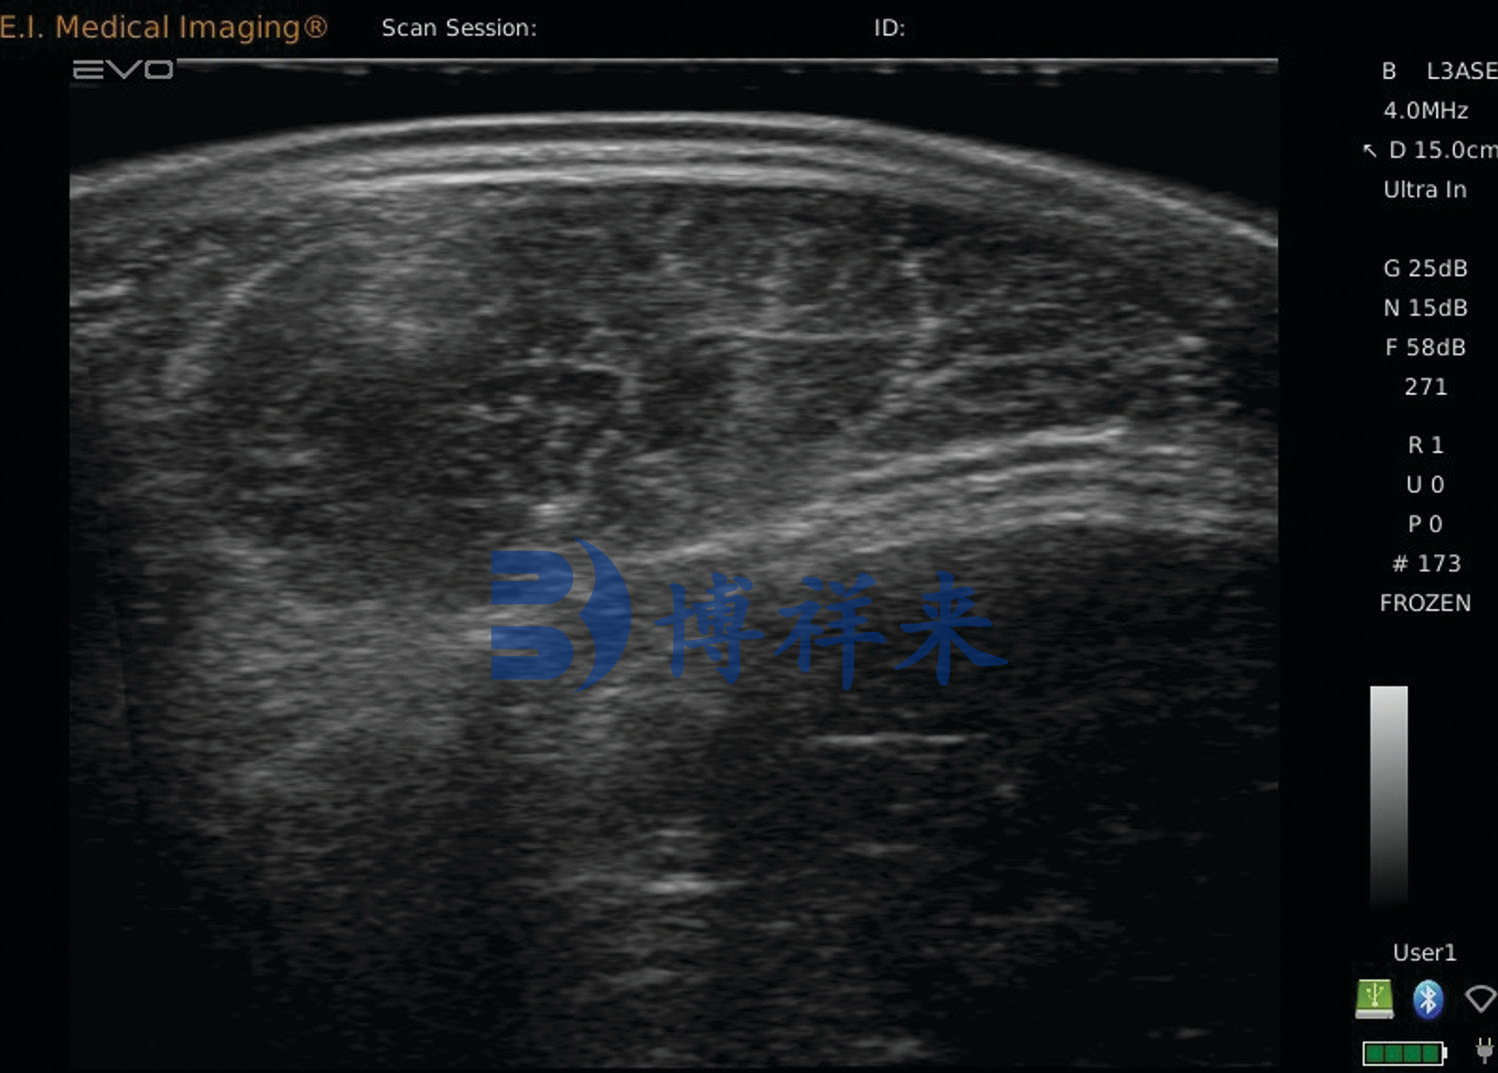

在传统养殖方式中,背膘厚度往往依赖经验判断或触摸估计,这种方式误差较大。而使用牛用B超机进行背膘检测,可以通过超声图像清晰看到皮肤层、脂肪层和肌肉层之间的结构,从而获得更加准确的测量数据。

利用兽用B超机进行眼肌面积测定,可以在牛只活体状态下观察背最长肌的轮廓,并通过设备软件进行面积计算,从而获得较为准确的数据。这一技术在国外肉牛育种体系中已经广泛应用,是现代肉牛性能测定的重要工具。

在实际检测过程中,技术人员通常在牛的第12—13肋骨之间进行扫描,这一位置是国际上常用的肉牛性能测定标准位置。通过超声图像可以清晰看到背最长肌的形态以及脂肪层厚度,并进行相应的测量。